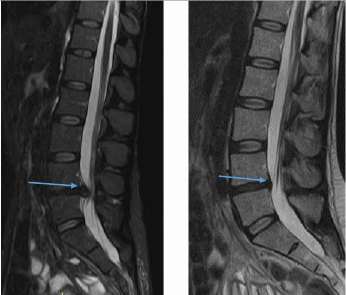

Институтом* разработаны принципы индивидуально подбора рецептуры процедур, которые являются индивидуальными для каждого пациента: разные суставы, разные ткани-источники болевого синдрома и разная окраска боли при ее восприятии. Зоны воздействия определяются при клиническом осмотре с учетом данных рентгена или МРТ, УЗИ сустава и околосуставных тканей.